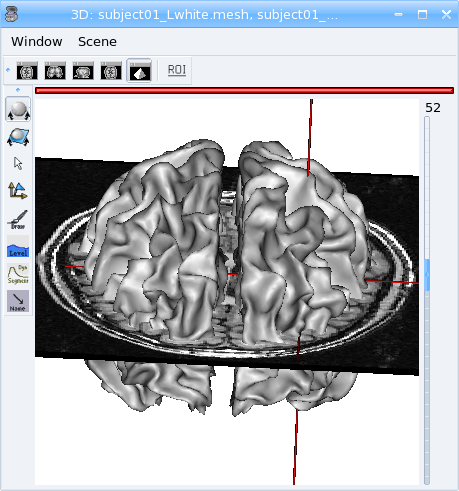

View meshes¶

Load:

data_for_anatomist/subject01/subject01_Lwhite.meshdata_for_anatomist/subject01/subject01_Rwhite.mesh

Open a 3D window by clicking on

.Put the objects into this window: drag and drop them into the 3d window.

View of white matter meshes in 3D window.¶